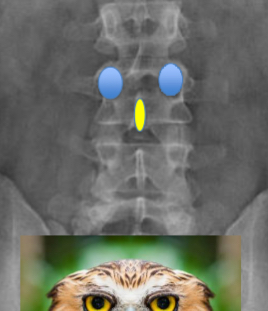

What are owl faces?

on AP projections all vertebrae should have an owl face

Eyes - pedicles, you should always see two of them

Beak - spinous process

Easiest to see in the lumbar spine but can be used throughout